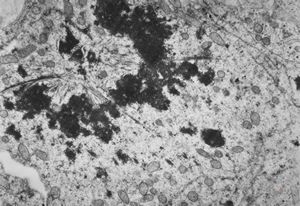

M,4y. | mitosis - retroperitoneal neuroblastoma